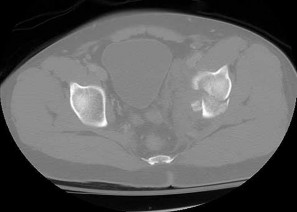

The injury pattern shown in the CT image in Figure 26 is most commonly associated with which mechanism?

Posterior shoulder dislocations are most commonly the result of seizures and electrical shock. Collision athletic events, postpolio syndrome, and traction injury are rarely associated with posterior shoulder dislocations. The bony defect caused by impaction of the anterior superior humeral head on the posterior glenoid has been referred to as a “reverse Hill-Sachs lesion.”